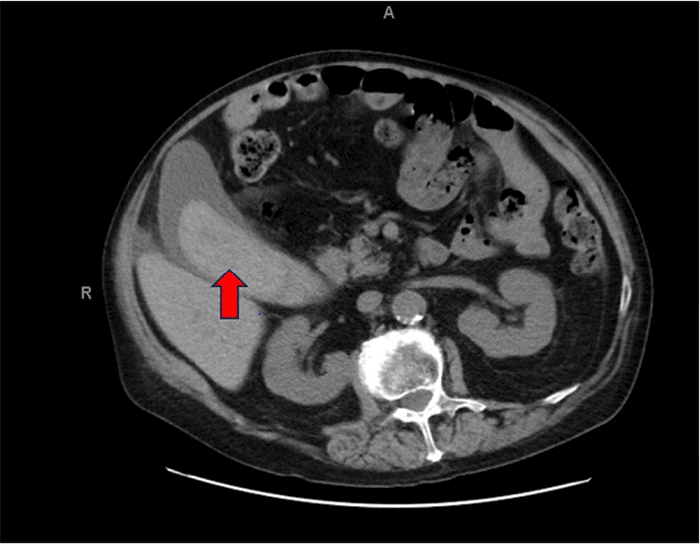

Figure 3. CT Angiography Revealing Features of Hemorrhagic Cholecystitis. Published with Permission

Axial image from a contrast-enhanced CTA of the abdomen, arterial phase. The gallbladder is markedly distended, and its lumen is predominantly occupied by high-attenuating material (red arrow), consistent with an intraluminal blood clot, characteristic of hemorrhagic cholecystitis

On physical exam, the patient was afebrile and hemodynamically stable. His abdomen exhibited mild RUQ tenderness on palpation; however, Murphy’s sign was absent, and there was no rebound tenderness or guarding. Initial laboratory evaluation revealed a mild anemia, while aminotransferase, alkaline phosphatase, and lipase levels were within normal limits. A computed tomography angiogram (CTA) of the abdomen and pelvis re-demonstrated significant gallbladder distension and showed non-enhancing, hyperdense material consistent with a large blood clot occupying approximately 75% of the gallbladder lumen, diagnostic of hemorrhagic cholecystitis (Figure 3). Additionally, a right-sided anterior diaphragmatic hernia, consistent with a Morgagni hernia, was incidentally found, containing omentum and loops of small bowel without evidence of obstruction (Figures 4 and 5). By the second day of admission, repeat laboratory tests showed a new elevation in liver enzymes (AST 130 IU/L, ALT 101 IU/L, alkaline phosphatase 250 IU/L) and a decline in hemoglobin from 10.7 to 9.0 g/dL. Following a multidisciplinary conference involving hematology, neurology, and perioperative care services, a decision was made to proceed with urgent surgical intervention.